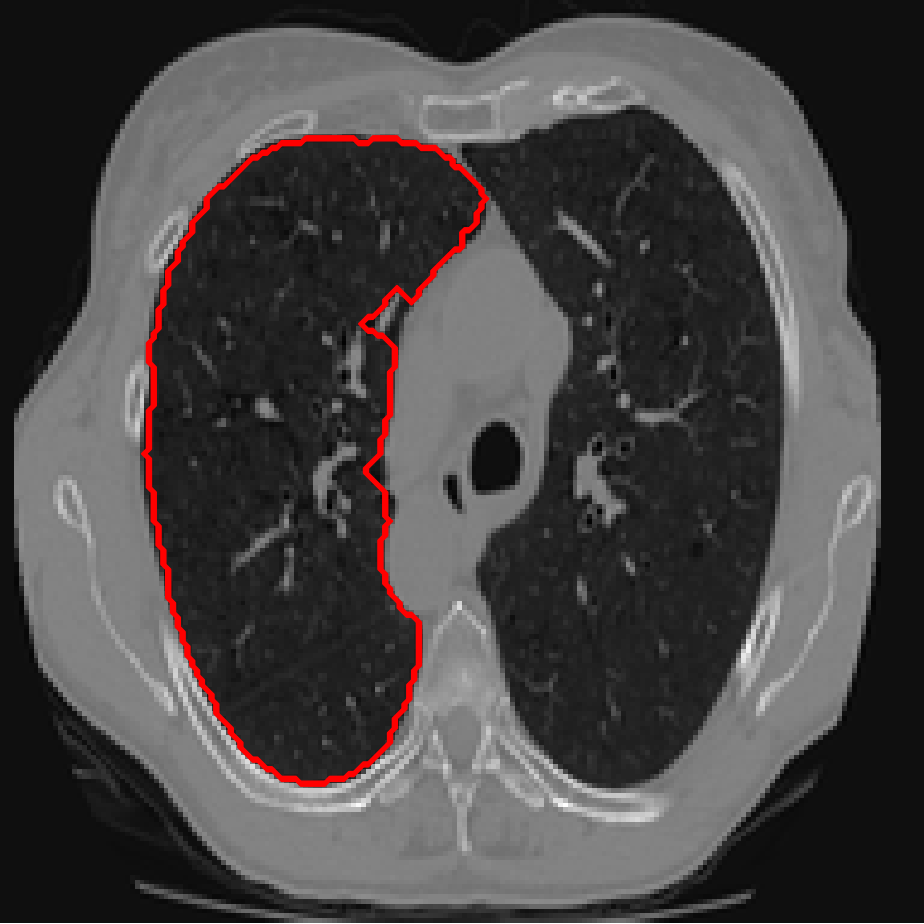

Figure 4: A sample result on the Lung data. We display the input image with the user input \mathcal{M}, the ground truth (GT) and results from the four methods. Moreover, we show comparisons with the model (4) solved in a variational framework with both Total Variation (TV) and Euler Elastica as explicit regularisation, as well as a comparison with the model solved in a Deep Image Prior framework.

In Figures 3 and 4 we show two select images from the test set for the Lung images to qualitatively show some results. To begin, we show some results of the model (1) solved with a Total Variation (TV) [21] regulariser, and with a Euler Elastica [22] regulariser. In addition, we show a result with the model (1) in a typical Deep Image Prior framework (i.e. training a network specifically for that image without the explicit regularisation in the loss function, employing early stopping). We see that the result from M4 is an improvement over the TV and Elastica models, whereas results from the DIP example is comparable. However, the DIP example requires a new network trained specifically for the new image, whereas our result is acquired after training. In addition to the explicit regularisation comparison, we also display the results from the four methods (all of which are trained previously on 222 images and used for prediction). Moreover some quantitative results are shown in table 1, which shows the mean DICE score and standard deviation on the 16 images in the test set.